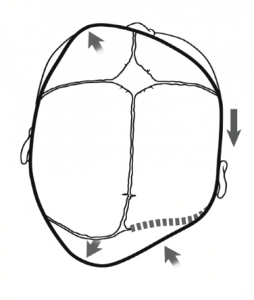

What does Plagiocephaly look like?

What does the presentation of plagiocephaly look like?

In positional plagiocephaly, there is a head preference to one side.

This can lead to increased pressure on that side of the head, leading to the flattening at the back part of the skull (occiput) on that side.

This is turn can lead to a change in the shape of the rest of the skull, with pushing forward (anterior) of the ear on the same side.

The bone at the front of the skull may then be pushed forward on the same side as the flattening, and the anterior ear.

In more severe cases there will be changes to facial structure, such as the cheek bones, and the eyes (orbits).

This is the typical positional plagiocephaly shape changes. This must be differentiated from the shape changes associated with synostotic plagiocephaly, which has a different appearance (see picture 2).